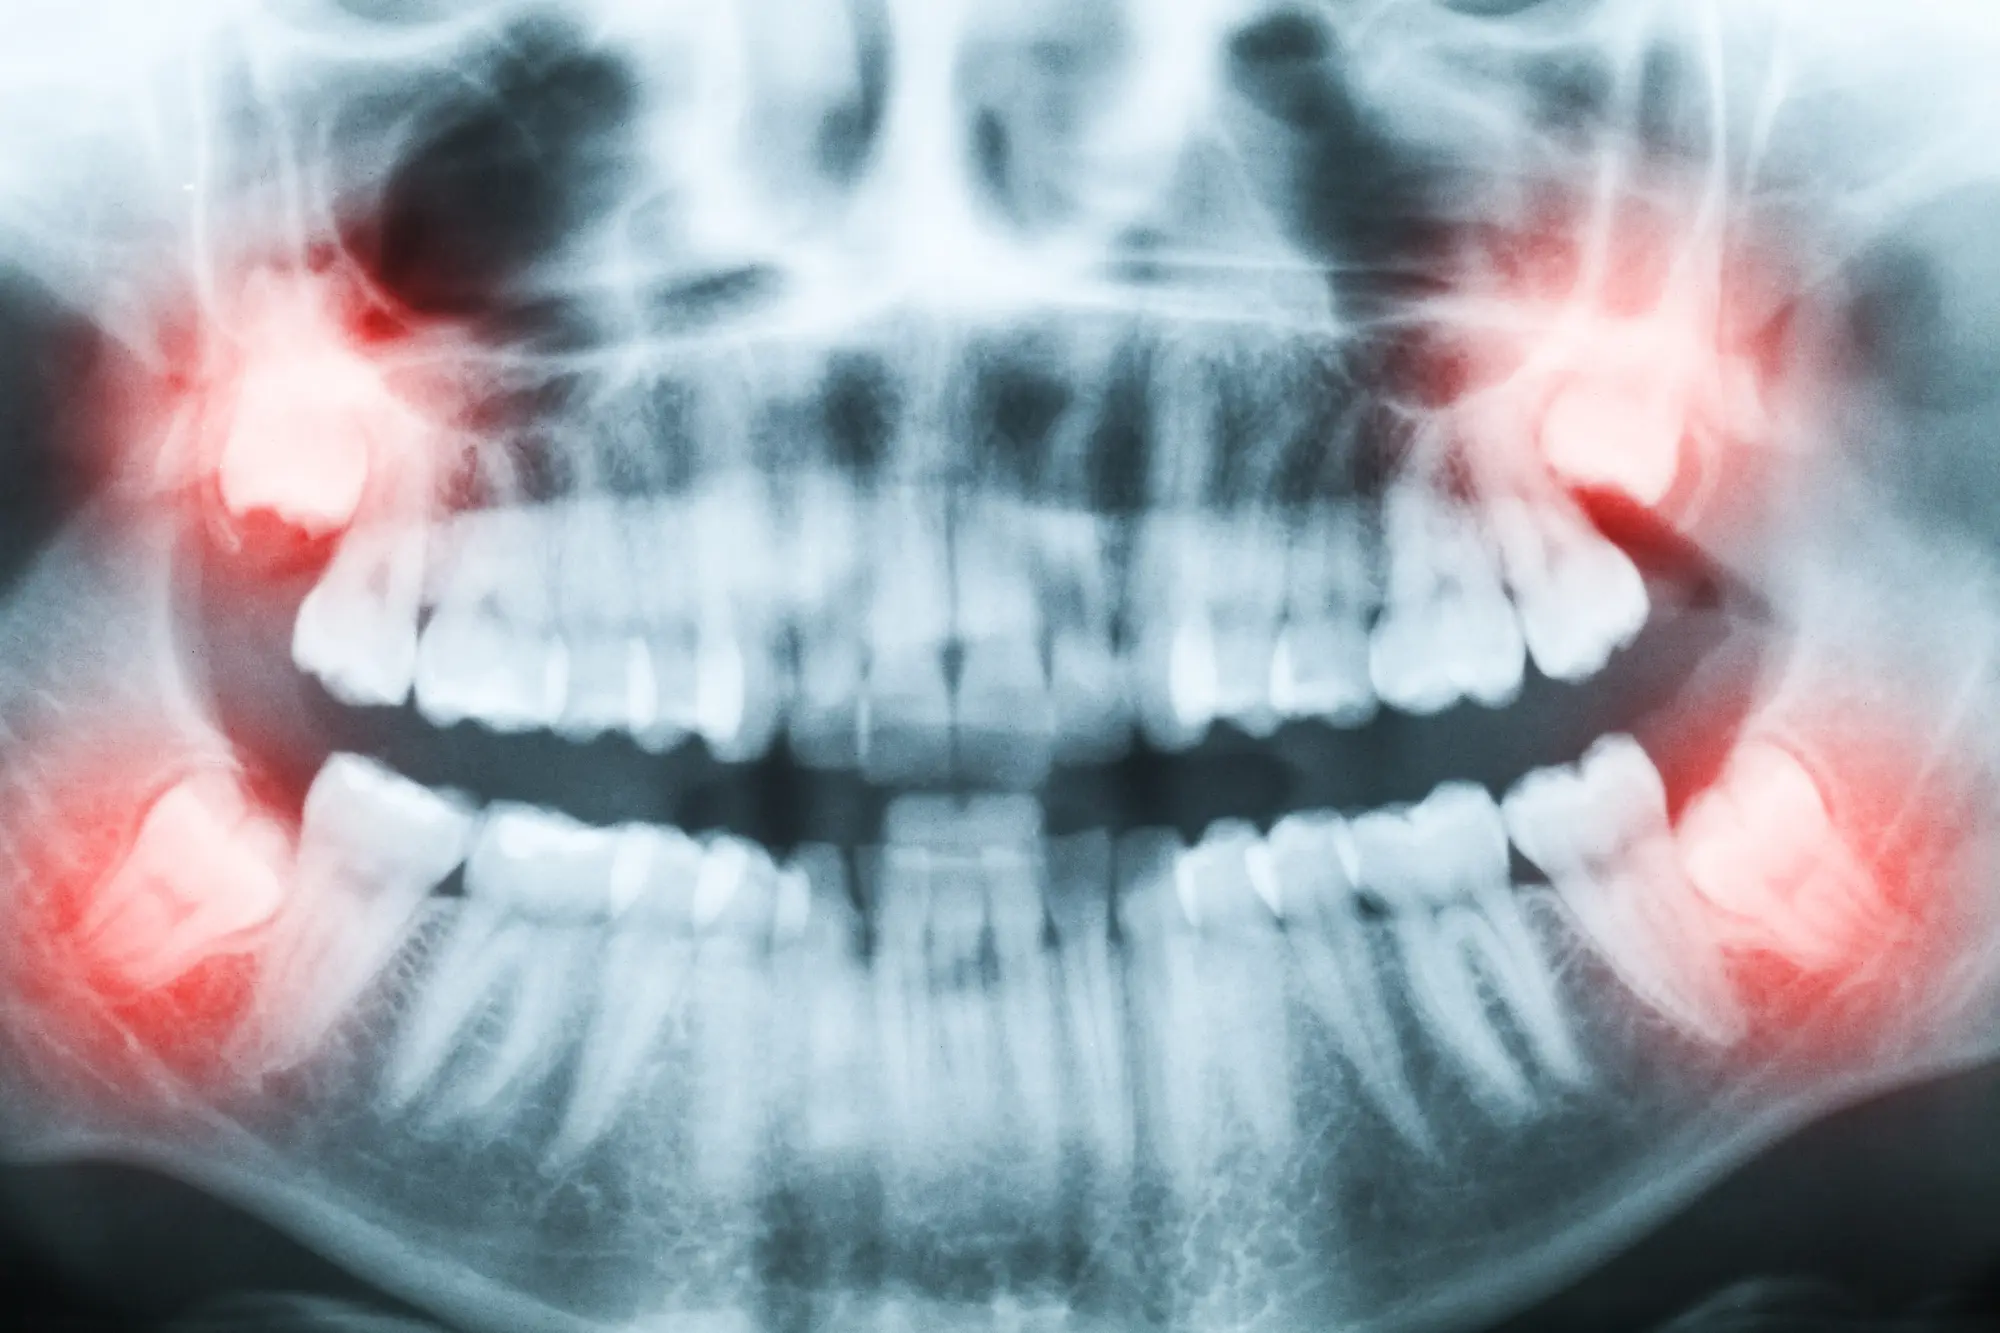

Post-Op Instructions After Wisdom Teeth Removal

After having your wisdom teeth removed, following the right post-surgery instructions is key to a smooth and speedy recovery. We’ve compiled important steps and tips to help guide you through the process.